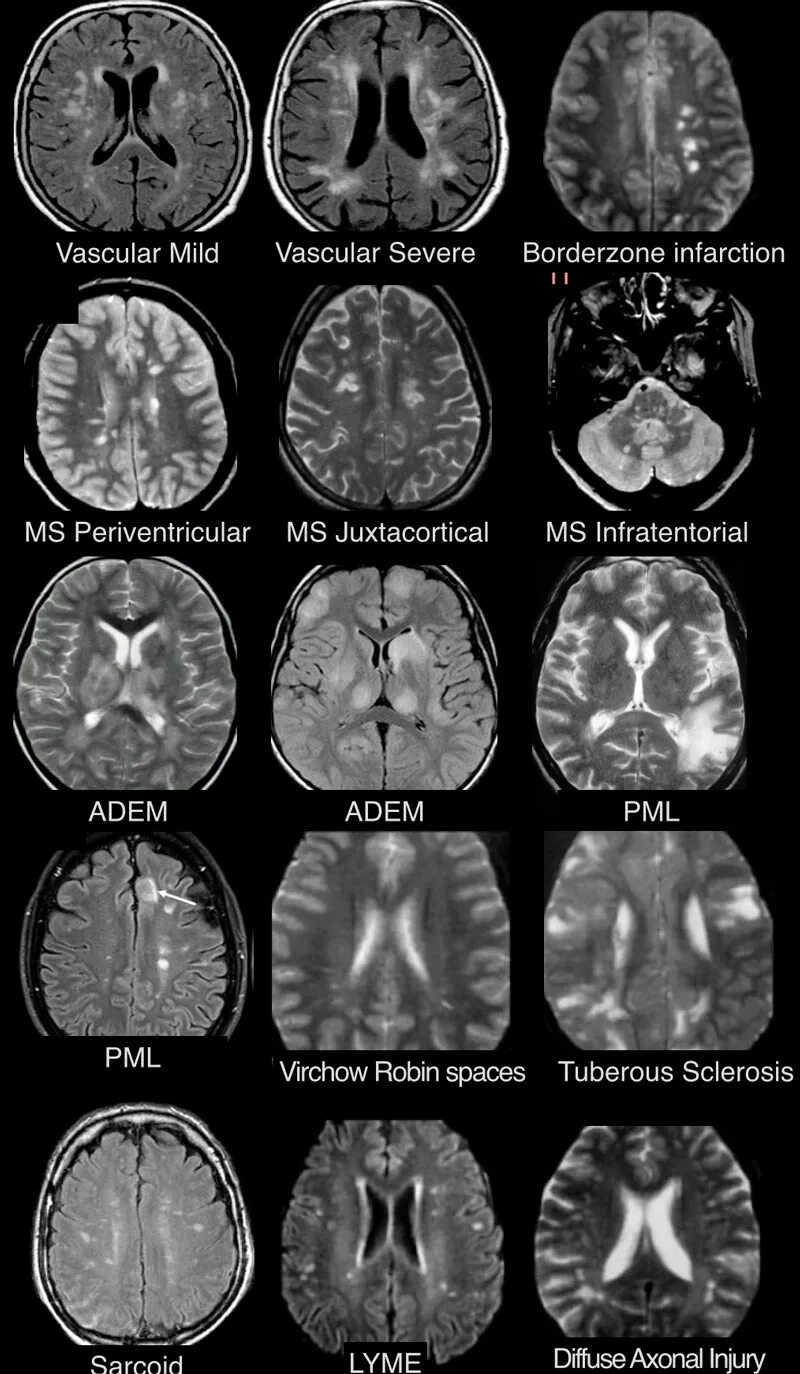

Что значит очаг в головном мозге